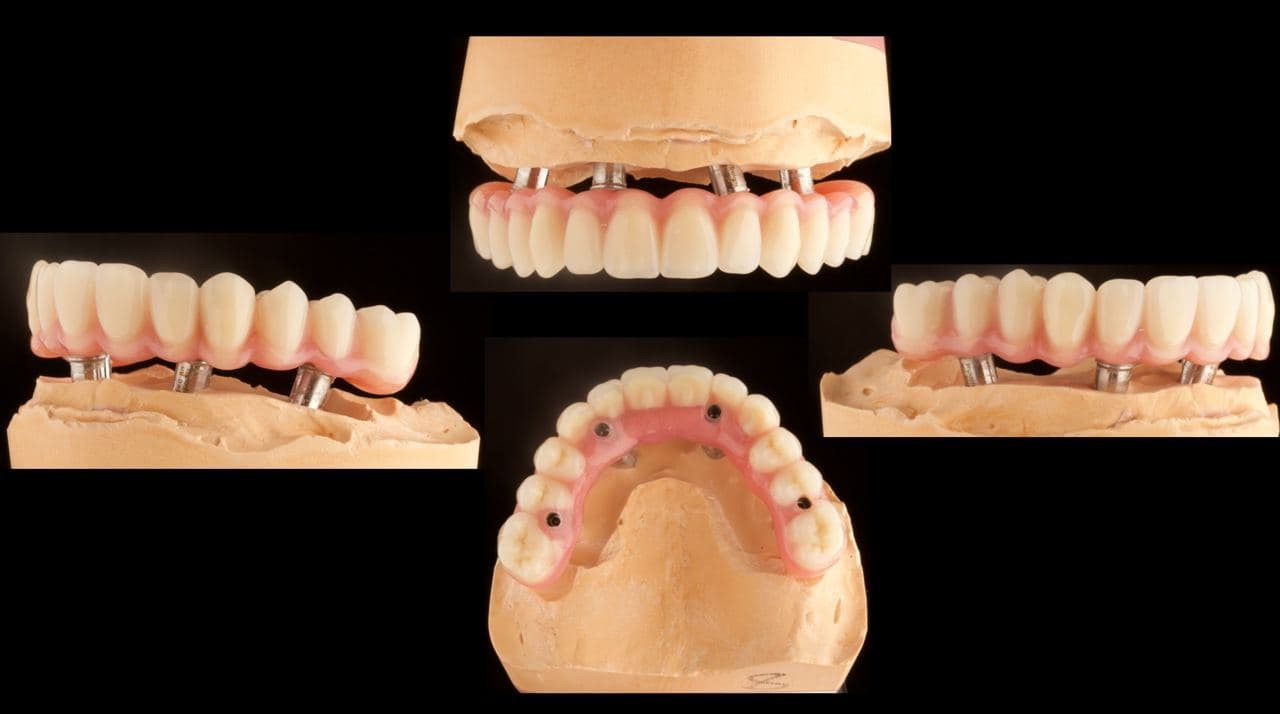

4. Мы собираем консилиум, планируем операцию и расположение имплантов, делаем по координатам двух исследований временную конструкцию (протезы зубов на полгода ношения), печатаем её и навигационные шаблоны на нашем 3D-принтере в клинике.

6. Следующим утром пациент приходит, засыпает в кресле под присмотром анестезиолога, мы удаляем все верхние зубы, прикладываем навигационный шаблон, вкручиваем заранее спроектированные импланты в места по шаблону, насыпаем графт экзогенной костной ткани вокруг двух участков, фиксируем ткани и ставим сверху временную конструкцию.

Временная конструкция на свежие импланты — не самая стабильная вещь. Первые две недели в такой ситуации нужно есть уже пережёванную пищу вроде пюре, каш и мягких котлет, пока не закрепятся импланты. Полностью интеграция достигается за несколько месяцев, обычно за четыре-шесть, плюс ещё прогресс медленно идёт до полугода. В это время нельзя есть ничего твёрдого вроде леденцов, потому что усилием больше 35 килограммов можно сломать пластик конструкции. В данном конкретном случае импланты прижились хорошо, с костью всё было в порядке, пациент через полгода перешёл на постоянную конструкцию (мы просто сняли временную и поставили в её слот постоянную, это быстро) из более прочного и долговечного материала. «Постоянная» – это сильно сказано, она на 20–25 лет, реже — на 40. Но математическое ожидание подсказывает, что она будет работать пожизненно. То есть он ел котлеты две недели. Потом пять с половиной месяцев были противопоказаны целая морковь, сухари и орехи. Но на практике современный пластик очень прочный, и я даже знаю пациента, который открыл так бутылку с пивом с крышкой старой конструкции. Кстати, эти крышки — давний спонсор стоматологов по всему миру.